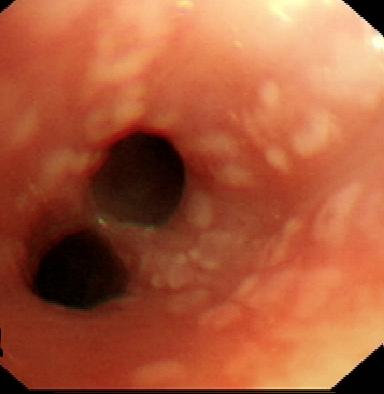

病例2王某,难治性哮喘3年,支气管镜下见散在粘膜小结节,经过检查确诊为”嗜酸性肉芽肿性血管炎”,经治疗后康复,复查支气管镜粘膜恢复正常。